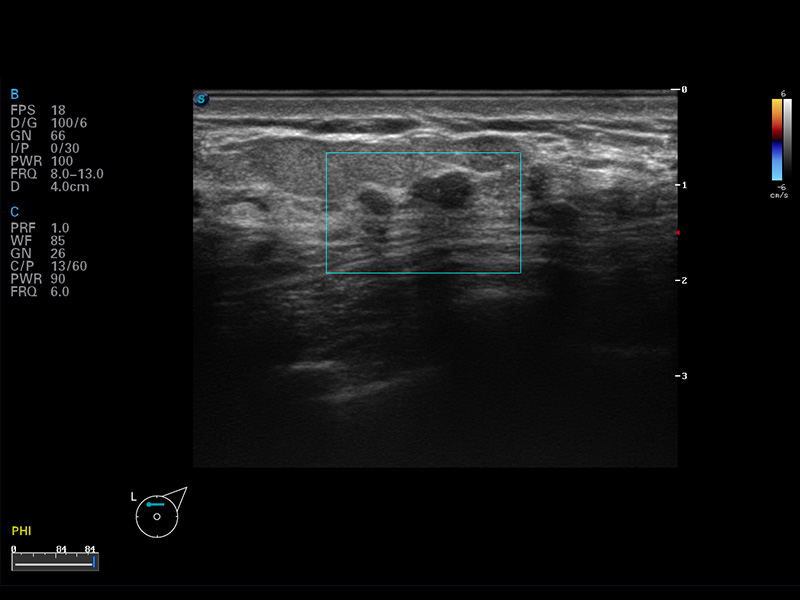

S8 EXP便携式彩色多普勒超声诊断仪是milan米兰研发的高端全身应用型便携彩超。高通道的VIS平台融合可视化(Visual)、智能化(Intelligent)和人性化(Smart)的特点,配以milan米兰自主研发生产的探头大家族,使您能够快速、准确的获得病人信息,提高工作效率的同时减轻疲劳。

μ-Scan微米成像

谐波成像

空间复合成像